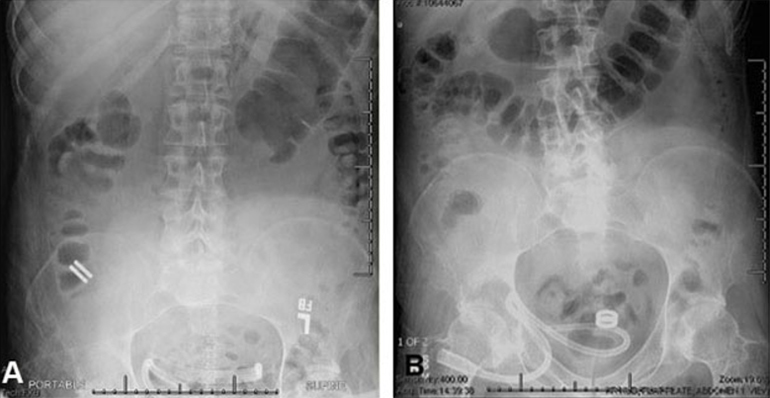

The study, led by Principal Investigator Michael Harrison, MD, is a prospective, single-center, first-in-human pilot clinical trial to evaluate the feasibility and safety of creating an intestinal anastomosis using the Magnamosis device. Magnetic compression anastomosis (magnamosis) uses a pair of self-centering magnetic "Harrison Rings" to create an intestinal anastomosis without sutures or staples. Each magnet is placed within the lumen of a desired segment of the intestine and brought together, or “mated.” The magnetic force on the compressed tissue causes necrosis and an anastomosis forms. The magnets then pass through the bowel.

In this first case series of the Magnamosis device in humans, we found that despite the complicated medical conditions and comorbidities of the 5 study participants, the device safely and successfully performed in every case. No patient experienced anastomotic leak, bleeding, or stricture formation.

The Magnamosis device's method of slow tissue remodeling without leaving foreign bodies creates a well-formed anastomosis, which can decrease the incidence of anastomotic leaks. In addition, the simplicity of merely “sticking” the 2 segments of intestine together can save substantial operative time. However, open operation is not the best way to showcase the merits of magnamosis. In our subsequent patients, we plan to focus on laparoscopic delivery of the Magnamosis device, which currently can be deployed using laparoscopic, endoscopic, radiographic, or hybrid techniques. In addition, the device can be sized and adapted to a variety of intraluminal anastomoses, including intestinal, urologic, and biliary applications, with wide-reaching implications for the future of surgery.